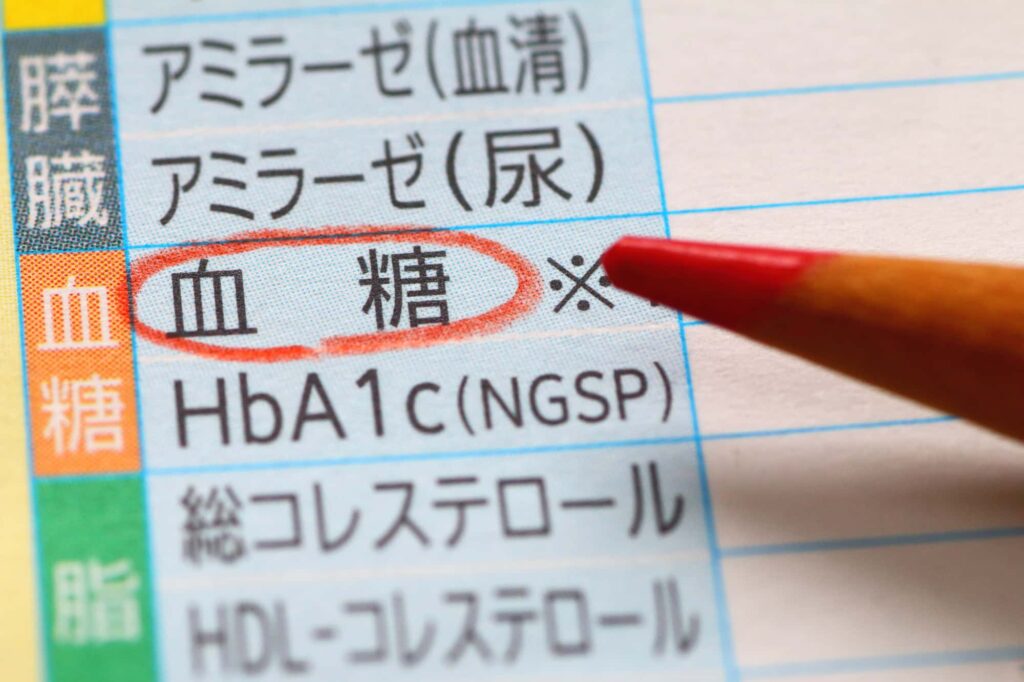

糖尿病とは、インスリンというホルモンの分泌量が不足したり、その働きが弱くなることによって、血液中のブドウ糖がうまく利用されず、高血糖の状態が続く病気です。血糖値が慢性的に高い状態は、全身の血管にダメージを与え、さまざまな合併症を引き起こすリスクがあります。

糖尿病は大きく分けて、1型・2型・妊娠糖尿病に分類されますが、最も多いのは生活習慣に起因する2型糖尿病です。食事の偏り、運動不足、肥満、ストレスなどが発症の要因として挙げられます。

初期は無症状であることも多く、検診などで偶然発見されるケースもあります。進行すると、喉の渇き、多尿、疲労感、視力低下などの症状が現れ、放置すれば腎臓や神経、目の病気など重大な合併症を引き起こす恐れがあります。

糖尿病は生活習慣の見直しと、適切な管理が必要不可欠な病気です。

歯周病の炎症によって体内に放出される炎症性サイトカインという物質が、インスリンの働きを阻害する作用を持つことがわかっています。これにより、血糖値のコントロールが難しくなり、糖尿病の管理がうまくいかなくなる可能性があるのです。

つまり、歯周病による全身的な炎症が、糖尿病の病態に悪影響を及ぼすというわけです。実際に、重度の歯周病を抱える糖尿病患者が歯周治療を受けたことで、HbA1c(ヘモグロビンA1c)の値が改善されたという研究報告もあります。

これは、口腔内の炎症を抑えることが、全身のインスリン抵抗性の改善につながる可能性を示しています。歯周病を治療することで血糖値が改善するという報告もあるため、糖尿病患者にとって口腔ケアは非常に重要なポイントといえます。